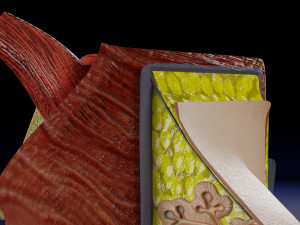

This is a 1:1 scaled model of right breast cut opened in sagittal plane to reveal its internal antomy and histology (schematic). The deeper parts and fascial layers are also depicted to give a very detailed approach to the model. The full layers starting from skin, nipple areola, till intercodtal muscles and ribs are also depicted.